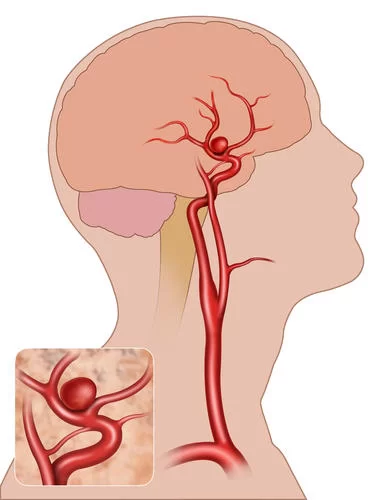

Το ανεύρυσμα εγκεφάλου είναι ένα εξόγκωμα, μια διόγκωση σε κάποιο αγγείο του εγκεφάλου. Με πολύ απλά λόγια, είναι ένα «μπαλόνι» σε επαφή με κάποια αρτηρία του εγκεφάλου (Εικόνα 1).